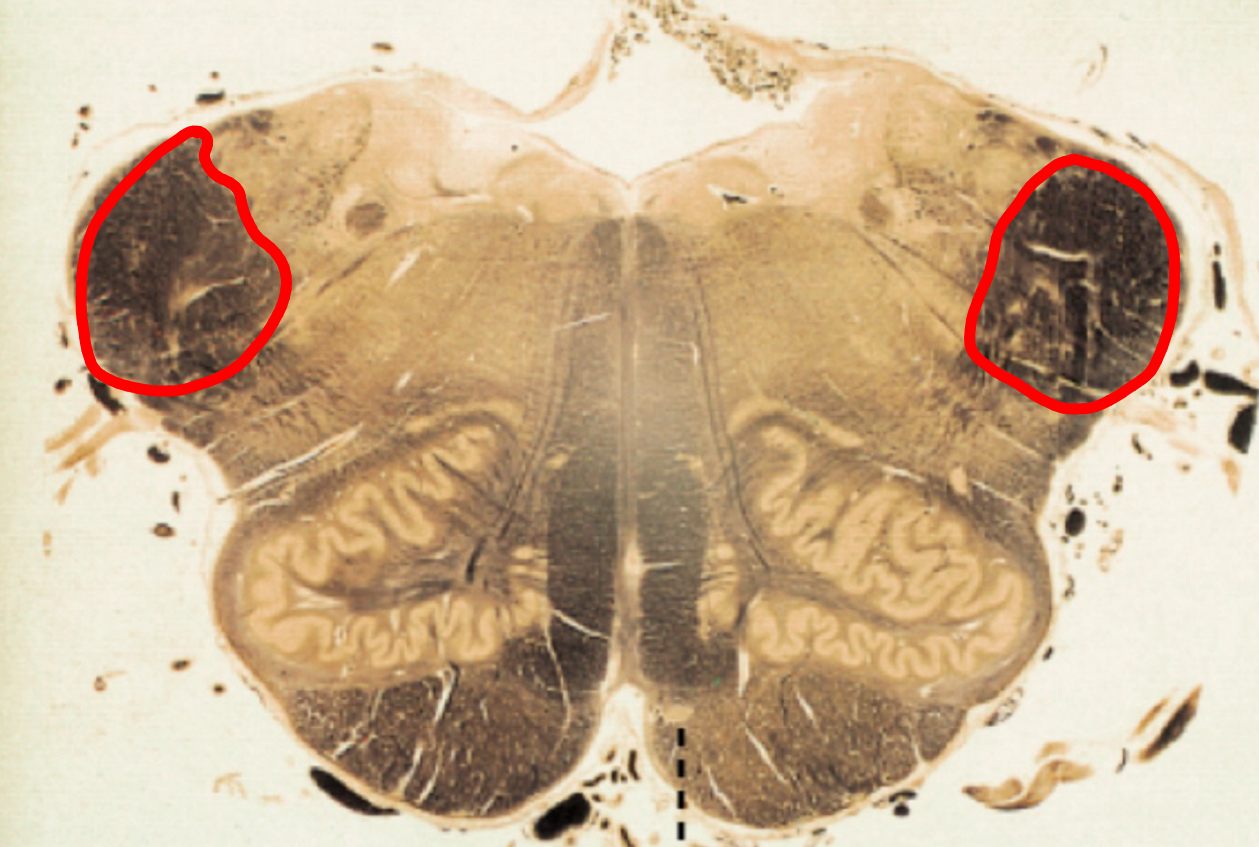

amygdaloid bodies